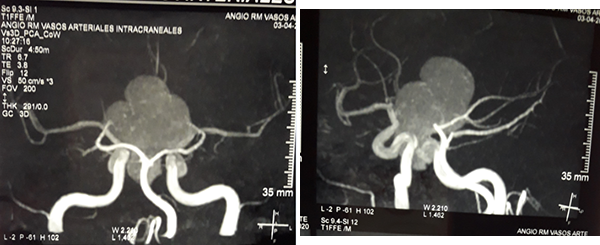

En RM de cerebro se observa lesión espacio ocupante selar-supraselar con aspecto multilobulado que invade cisterna interpeduncular y desplaza estructuras del tercer ventrículo. La misma es hiperintensa espontáneamente en T1 con captación heterogénea de contraste, hiperintensa en T2 (Figura 1). En secuencia de angioresonancia se observa su relación medial respecto a arterias carótidas no comprometiendo las mismas (Figura 2). A partir de éstas imágenes obtenidas en resonador 3 Tesla, en el Departamento de Innovación Tecnológica del Instituto Cardiológico de la Ciudad de Corrientes se realizó un proceso de segmentación de las distintas partes de interés (tumor, arterias, nervios ópticos y globos oculares). Para esto se utilizó el software “Open Source 3D Slicer (versión 4.11)” (Figura 3). Una vez segmentadas las regiones de interés, se realizó, mediante una impresora 3D “MAX” de la empresa Creatbot, un modelo 3D cuyos materiales consistieron en poliácido láctico (PLA) y poliuretano termoplástico (Figuras 4 y 5). Con el mismo, se realizó la planificación del abordaje quirúrgico.

Figura 1: RM en secuencia T1 cortes a) 1axial, se observa lesión espontáneamente hiperintensa y su relación con vasos del polígono de Willis. b) RM en secuencia T1 corte sagital, donde se observa extensión supraselar de la lesión comprimiendo lamina terminalis

Figura 2: RM en secuencia de angioresonancia a) proyección coronal posterior, observándose arterias cerebrales posteriores circunscribiendo la lesión b) proyección oblicua izquierda y su relación con arterias carótidas y ramas de bifurcación.